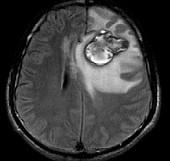

问题 男,34岁,3个月前行左额叶脑肿瘤切除术,近1个月又感头痛无恶心呕吐,近1周来又觉双下肢无力,并失语,请根据所提供图像,选择最可能的诊断()

选项 A.(左额叶)星形细胞Ⅱ级伴出血坏死(复发性) B.(左额叶)脑出血 C.(左额叶)海绵状血管瘤 D.(左额叶)动静脉血管畸形 E.(左额叶)脑肿瘤术后

答案 A